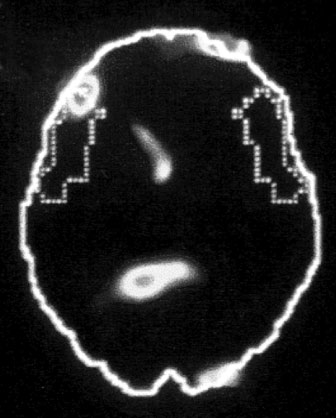

А. Правая лимбическая область

Б. Зрительная кора

В. Зона Брока

Изображение мозга в процессе переживания травмы. Светлые пятна в лимбической коре (А) и зрительной коре (Б) соответствуют повышенной активности мозга в этих участках. На снимке (В) видна значительно пониженная активность речевого центра мозга.

Когда через эту процедуру прошли все восемь участников, Скотт Рауч вместе со своими математиками и статистиками взялся за создание составного снимка, по которому можно было бы наглядно сравнить активность мозга в нейтральном состоянии и в момент появления неприятных воспоминаний. Несколько недель спустя он отправил мне результаты, которые вы видите выше. Я приклеил эти снимки на дверцу своего холодильника в кухне и на протяжении следующих нескольких месяцев каждый вечер их разглядывал. Должно быть, именно так чувствовали себя первые астрономы, взглянув через телескоп на неизученное звездное скопление.

На снимках были некоторые сбивающие с толку точки и цвета, однако самая яркая область активации мозга – большое красное пятно в правом нижнем центре мозга, известном как лимбическая область, или эмоциональный мозг, – никакого удивления не вызывала. Мы уже знали, что сильные эмоции активируют лимбическую систему, в особенности участок внутри нее, известный как миндалевидное тело.

Миндалевидное тело предупреждает нас о надвигающейся опасности, активируя стрессовую реакцию организма. Наше исследование явно показало, что у переживших травму людей определенные образы, звуки или мысли, связанные с их конкретными переживаниями, миндалевидное тело начинает бить тревогу – даже, как это было в случае с Маршей, спустя тринадцать лет после самого происшествия.

Больше всего из полученных нами результатов нас поразила белая точка в левой фронтальной доле коры, так называемой зоне Брока. В данном случае изменение цвета означает значительный спад активности в этой области мозга.

Зона Брока – это один из речевых центров мозга, который зачастую бывает затронут у людей, перенесших инсульт, когда этот участок оказывается отрезан от кровотока. Без нормально функционирующей зоны Брока человек неспособен выражать словами свои мысли и чувства. Наши снимки показали, что при активации болезненных воспоминаний зона Брока отключалась.

Когда слова подводят, центральное место в переживаниях занимают навязчивые образы, которые впоследствии преследуют нас в виде ночных кошмаров и болезненных живых воспоминаний. Если у наших участников отключалась зона Брока, то другой участок мозга под названием поле Бродмана 19[16] в этот момент активировался. Эта область зрительной коры регистрирует образы, когда они впервые попадают в мозг. Мы были удивлены увидеть активацию этой области спустя столь долгое время после изначально пережитой травмы. Обычно необработанные образы, зарегистрированные в поле 19, быстро распределяются по остальным участкам мозга, которые пытаются осмыслить увиденное. Опять-таки, мы стали свидетелями того, как участок мозга зажигается, словно человек переживает свою психологическую травму прямо сейчас.

Снимки также показали, что во время этих живых болезненных воспоминаний у наших подопытных активировалась лишь правая часть мозга. В настоящий момент имеется множество научной и популярной литературы на тему различий между правым и левым полушарием. В начале девяностых мне доводилось слышать, что кто-то начал делить мир на людей с развитым левым (преобладает рациональное мышление, логика) и правым (интуиция, творческие способности) полушариями, однако тогда я не придал этой идее особого значения. Тем не менее наши снимки явно демонстрировали, что образы о пережитой травме активируют правое полушарие мозга, отключая при этом левое.